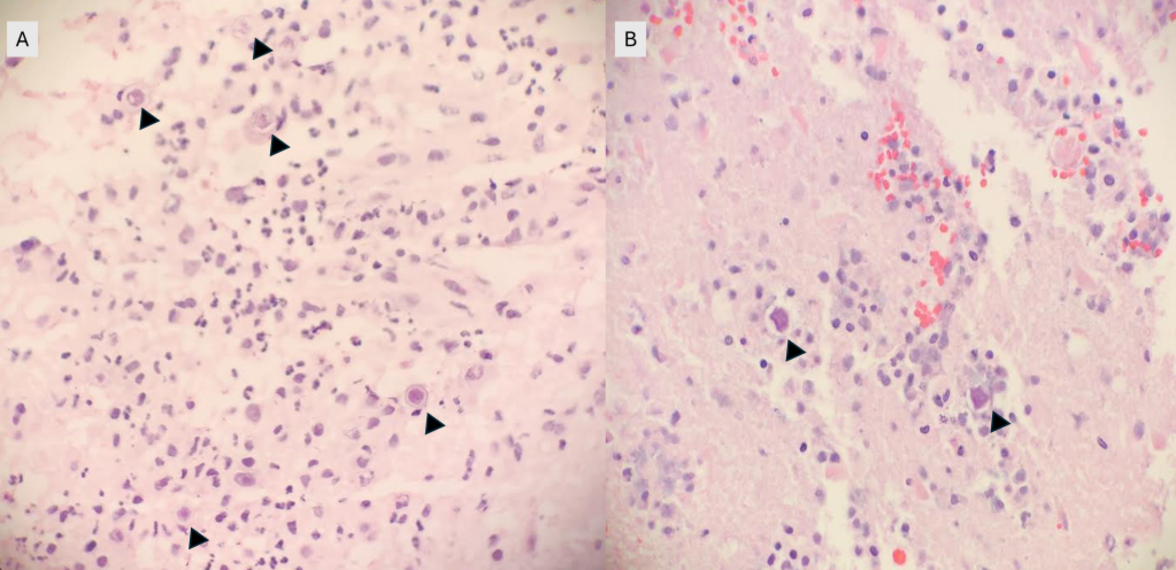

Срезы биоптата выявили выраженную некротическую ткань мозга с амебными цистами и трофозоитами, соответствующими свободноживущим амебам (илл.1). Цитология цереброспинальной жидкости (ЦСЖ) была без особенностей. Был проведен специфический иммуногистохимический анализ на виды Acanthamoeba, подтвердивший диагноз гранулематозного амебного энцефалита, вызванного Acanthamoeba.

Иллюстрация 1. Срезы биоптата демонстрировали амебные цисты (наконечники стрелок) на фоне некроза, кровоизлияния и воспаления (400-кратное увеличение).